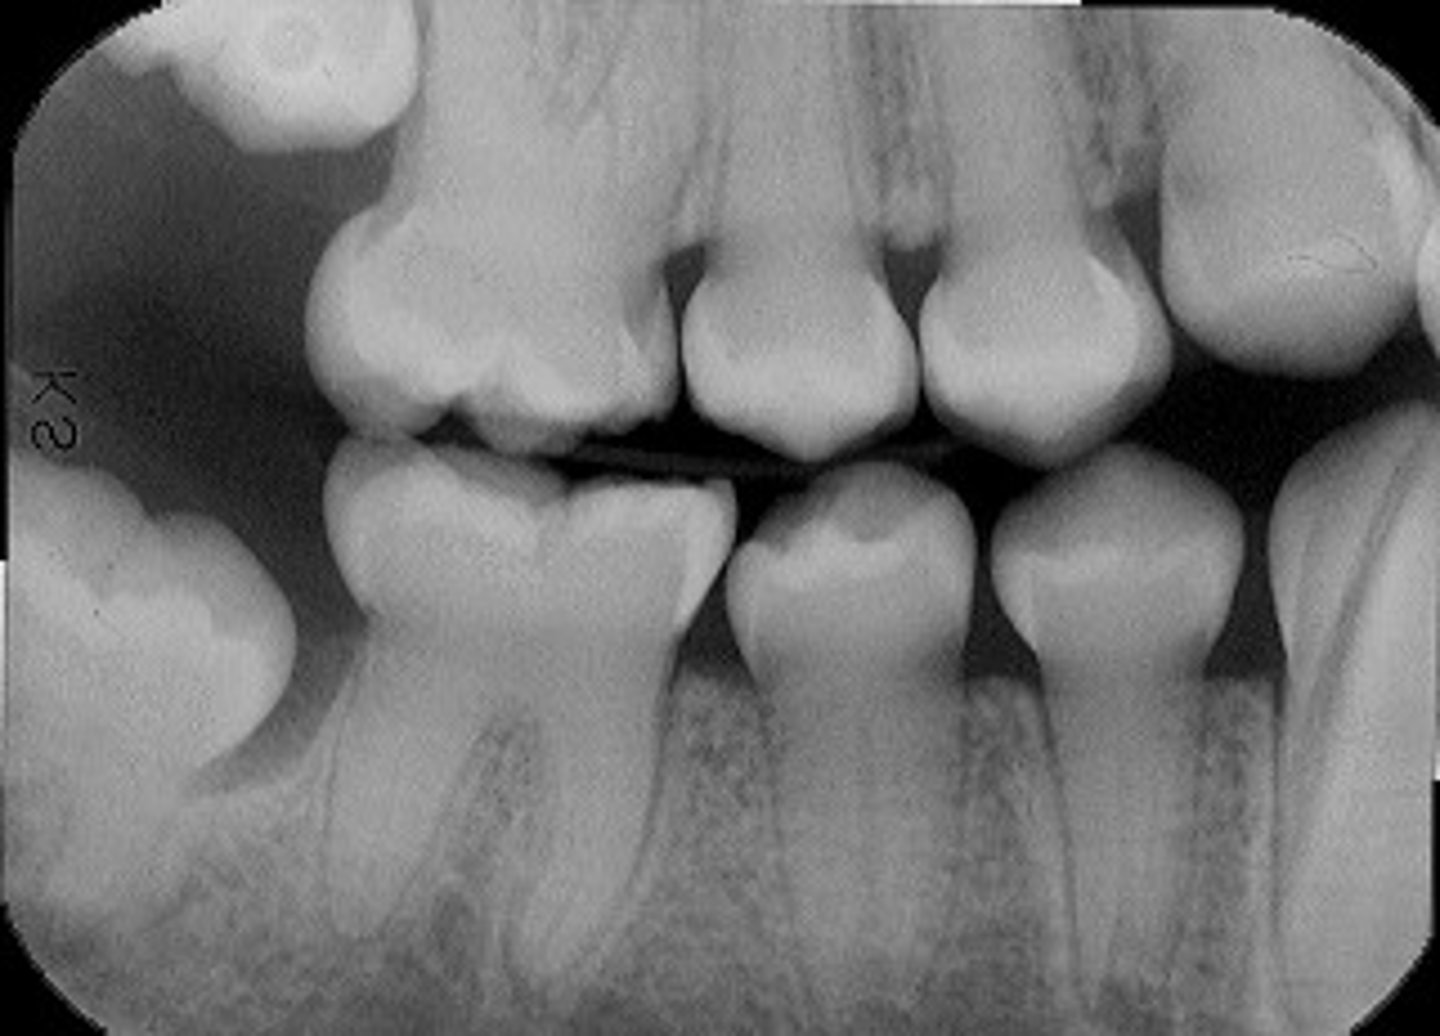

bone loss on #4

crater defect